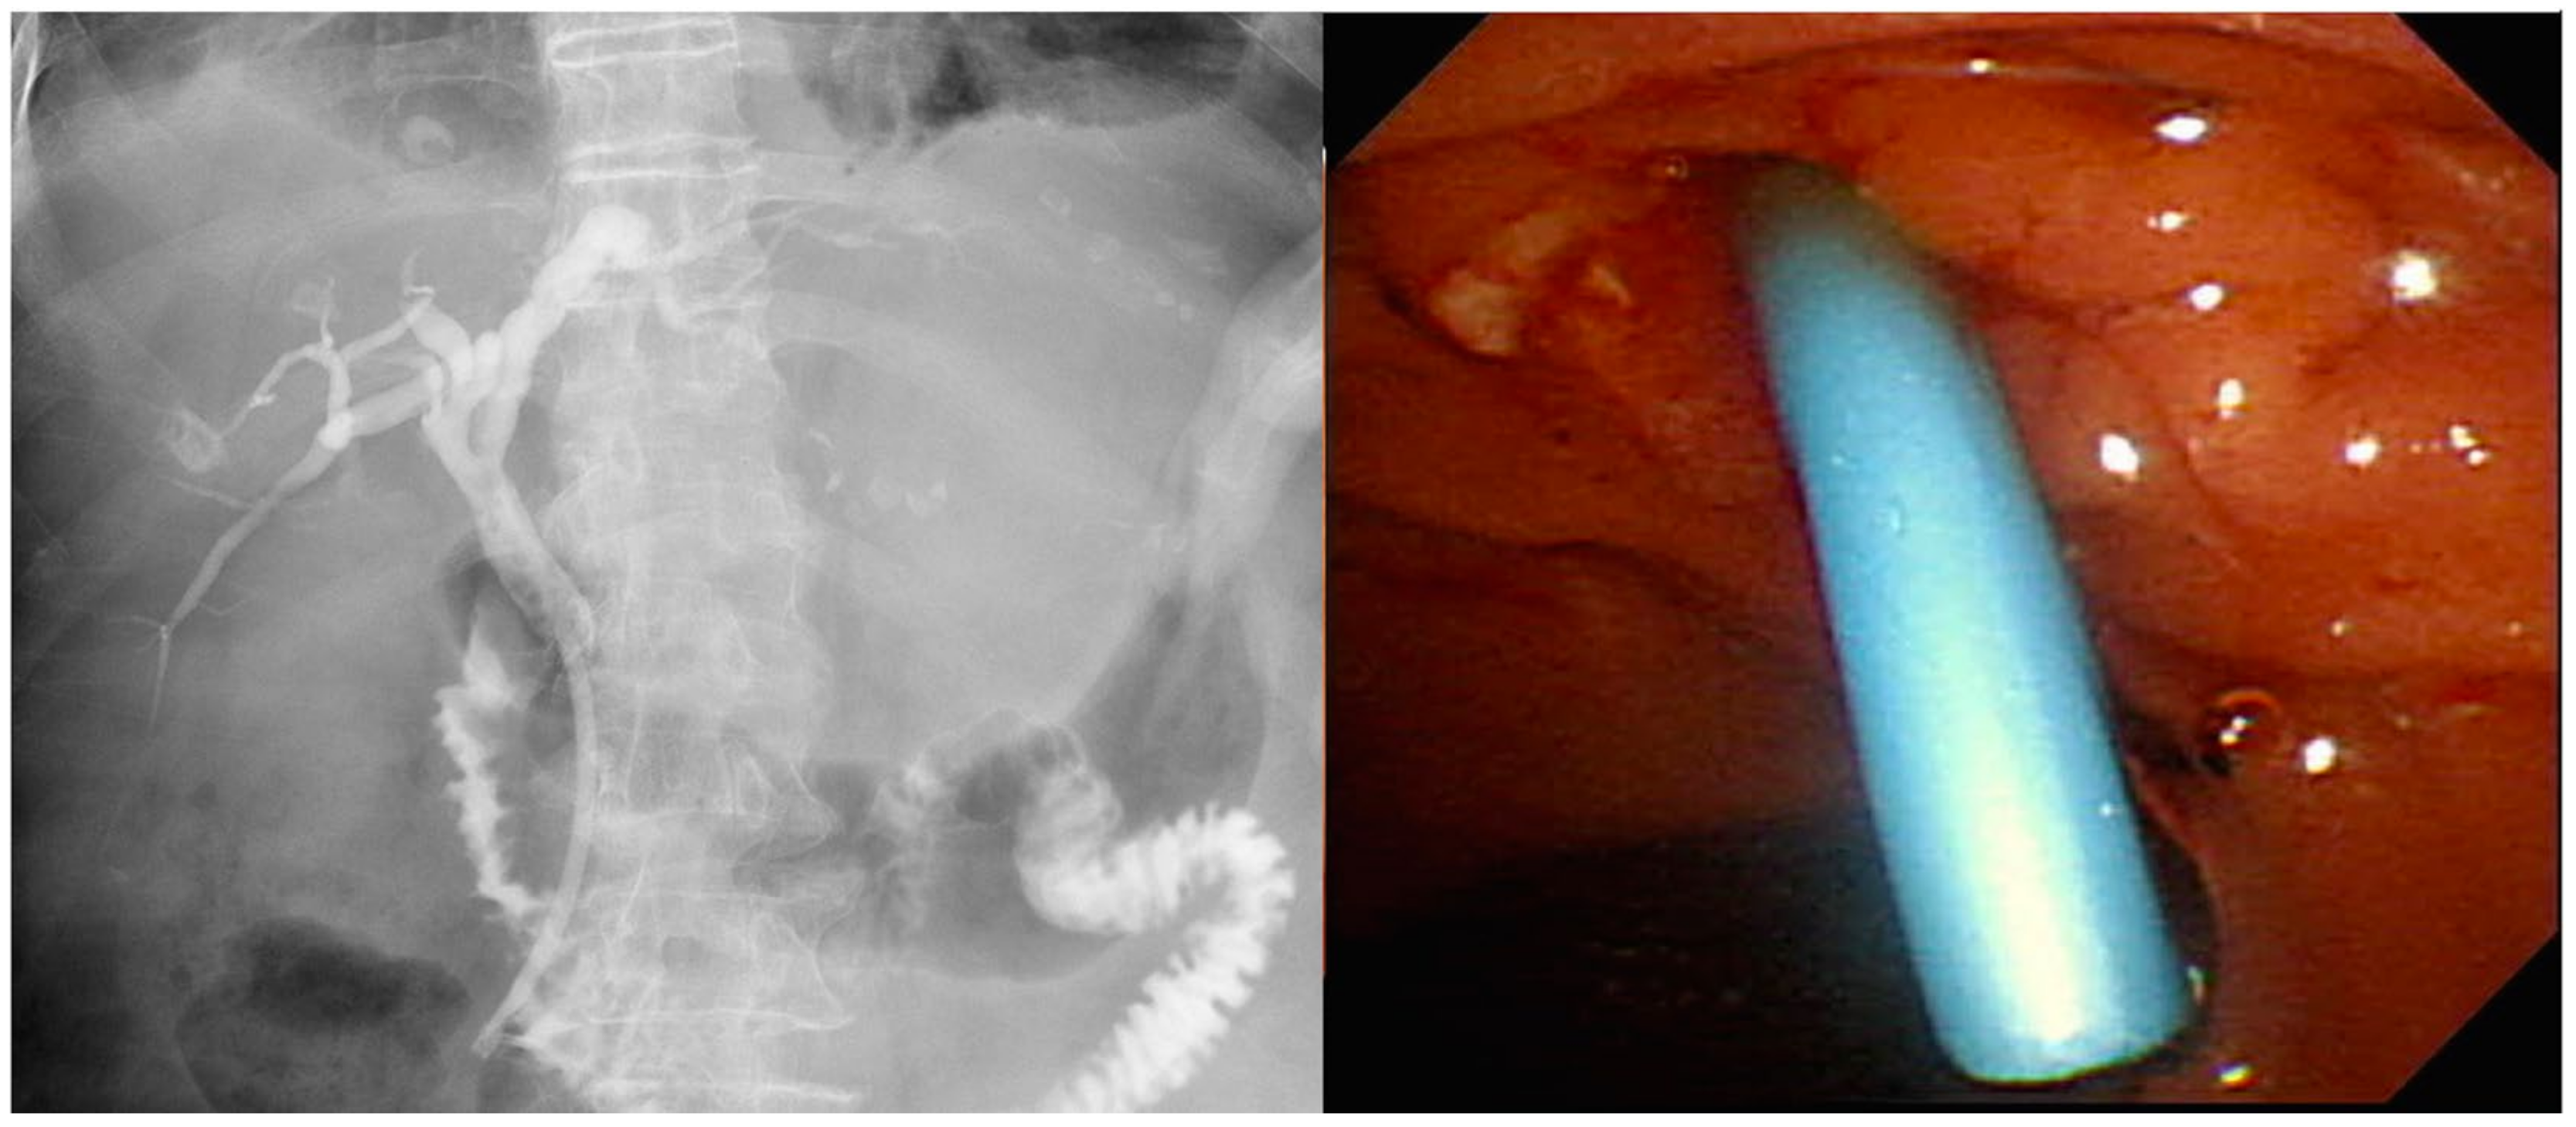

3.2. Stent Selection

- Isayama, H.; Nakai, Y.; Kawakubo, K.; Kogure, H.; Hamada, T.; Togawa, O.; Sasahira, N.; Hirano, K.; Tsujino, T.; Koike, K. Endoscopic retrograde cholangiopancreatography for distal malignant biliary stricture. Gastrointest. Endosc. Clin. N. Am. 2012, 22, 479–490. [Google Scholar] [CrossRef]

- Lee, J.H. Self-expandable metal stents for malignant distal biliary strictures. Gastrointest. Endosc. Clin. N. Am. 2011, 21, 463–480. [Google Scholar] [CrossRef]

- Jaganmohan, S.; Lee, J.H. Self-expandable metal stents in malignant biliary obstruction. Expert Rev. Gastroenterol. Hepatol. 2012, 6, 105–114. [Google Scholar] [CrossRef]

- Knyrim, K.; Wagner, H.J.; Pausch, J.; Vakil, N. A prospective, randomized, controlled trial of metal stents for malignant obstruction of the common bile duct. Endoscopy 1993, 25, 207–212. [Google Scholar] [CrossRef] [PubMed]

- Prat, F.; Chapat, O.; Ducot, B.; Ponchon, T.; Pelletier, G.; Fritsch, J.; Choury, A.D.; Buffet, C. A randomized trial of endoscopic drainage methods for inoperable malignant strictures of the common bile duct. Gastrointest. Endosc. 1998, 47, 1–7. [Google Scholar] [CrossRef]

- Katsinelos, P.; Paikos, D.; Kountouras, J.; Chatzimavroudis, G.; Paroutoglou, G.; Moschos, I.; Gatopoulou, A.; Beltsis, A.; Zavos, C.; Papaziogas, B. Tannenbaum and metal stents in the palliative treatment of malignant distal bile duct obstruction: A comparative study of patency and cost effectiveness. Surg. Endosc. 2006, 20, 1587–1593. [Google Scholar] [CrossRef] [PubMed]

- Soderlund, C.; Linder, S. Covered metal versus plastic stents for malignant common bile duct stenosis: A prospective, randomized, controlled trial. Gastrointest. Endosc. 2006, 63, 986–995. [Google Scholar] [CrossRef] [PubMed]

- Levy, M.J.; Baron, T.H.; Gostout, C.J.; Petersen, B.T.; Farnell, M.B. Palliation of malignant extrahepatic biliary obstruction with plastic versus expandable metal stents: An evidence-based approach. Clin. Gastroenterol. Hepatol. 2004, 2, 273–285. [Google Scholar] [CrossRef]